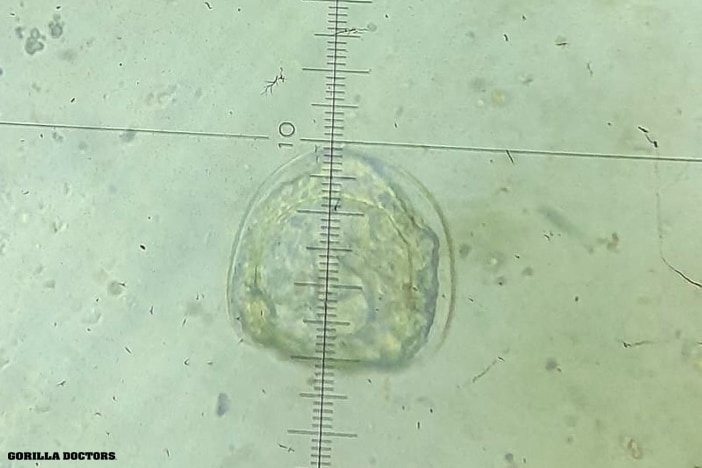

Microscopic image of a parasite in a baboon sample. © Gorilla Doctors

A: We used coproscopy, which is looking at the samples under a microscope. We also utilized real-time PCR genetic sequencing to identify individual Strongyloides at the species level. This was the first-ever attempt to genetically identify the different species. Previous studies mainly used coproscopy only. By combining both techniques, we can provide much stronger evidence for parasite identity and cross-host overlap. In fact, the study uncovered much higher parasite prevalence than previously detected and revealed how these infections cross species boundaries. It really highlighted the importance of molecular diagnostics in wildlife disease surveillance for us.